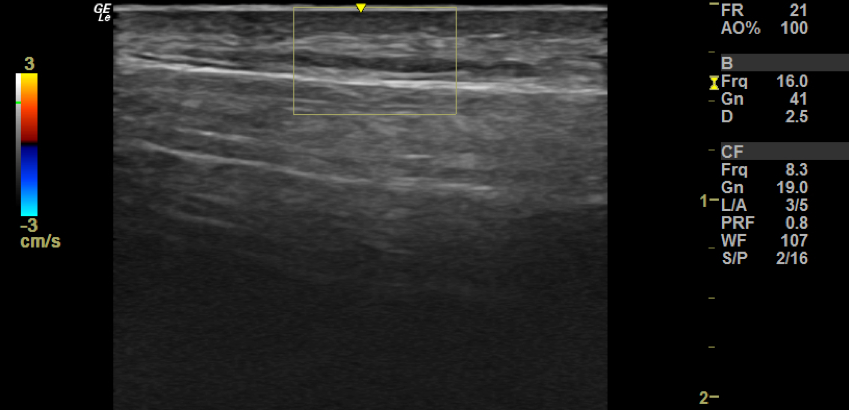

Left lateral malleolus. Going proximal, following a terminal branch of the superficial peroneal nerve.

Longitudinal view:

At the point of the positive tinel´s, there is a short segement swelling of a branch of the superficial peroneal nerve.

However, as we go proximally, we suddenly see swelling of one, an then swelling of the other fascicle of this part of the nerve….

Longitudinal view (without any detectable vascularization):